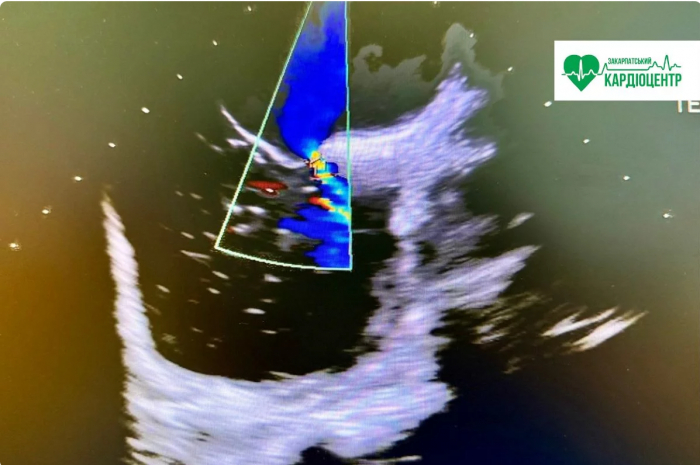

— Бабл-тест, або bubble test, — це різновид ехокардіографії з невеликим «секретом». Під час дослідження ми вводимо у вену фізіологічний розчин, збовтаний до утворення мікробульбашок. Вони абсолютно безпечні, добре візуалізуються на ехокардіографії й допомагають побачити те, що інколи залишається «невидимим» при звичайному УЗД серця.

— Надзвичайно важливу. Бабл-тест у нашому кардіоцентрі виконують на УЗД-апараті експертного класу. Це дає змогу отримати максимально чітке зображення й значно підвищує точність діагностики.